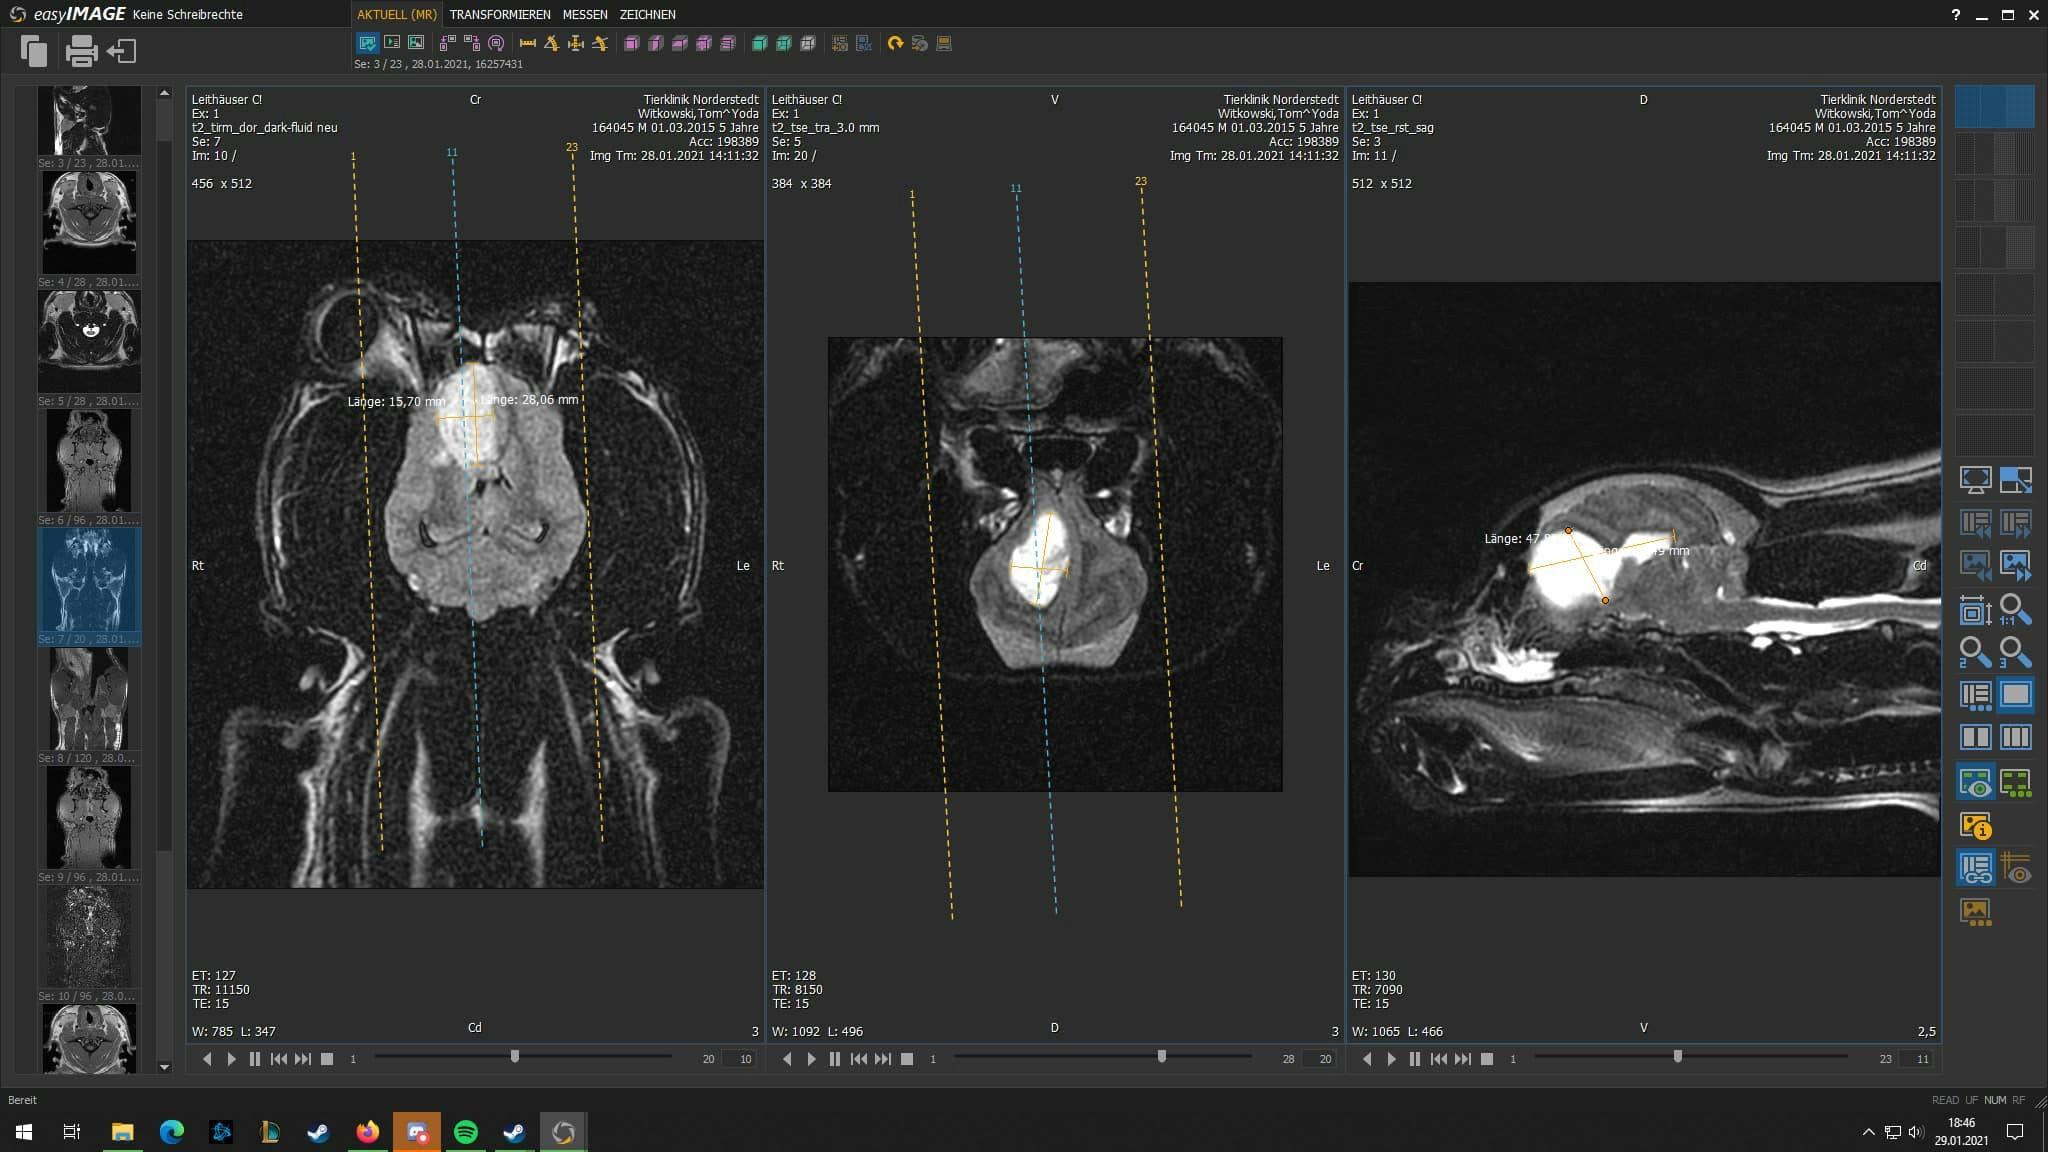

The next morning we waited for the call from the neurologist and it was like an eternity. At 11:30 the clinic called and said that they need to do an MRT for a real diagnosis. It could be meningitis or a brain tumor. Another endless wait later at 15:00 the MRT was done. Result: very bad - a large brain tumor and chance of healing ~0.

At the clinic the neurologist showed us the MRT images - it was a quarter of his brain. ๐ฑ After this Yoda walked into the room like nothing happened - a real hero. The neurologist was surprised. But he hasn't recognized me or my girlfriend - just walked rounds in the room. The neurologist left us alone with Yoda. We made some last paw prints ๐พ, photos and videos, cuddled a lot and couldn't hold back our tears.